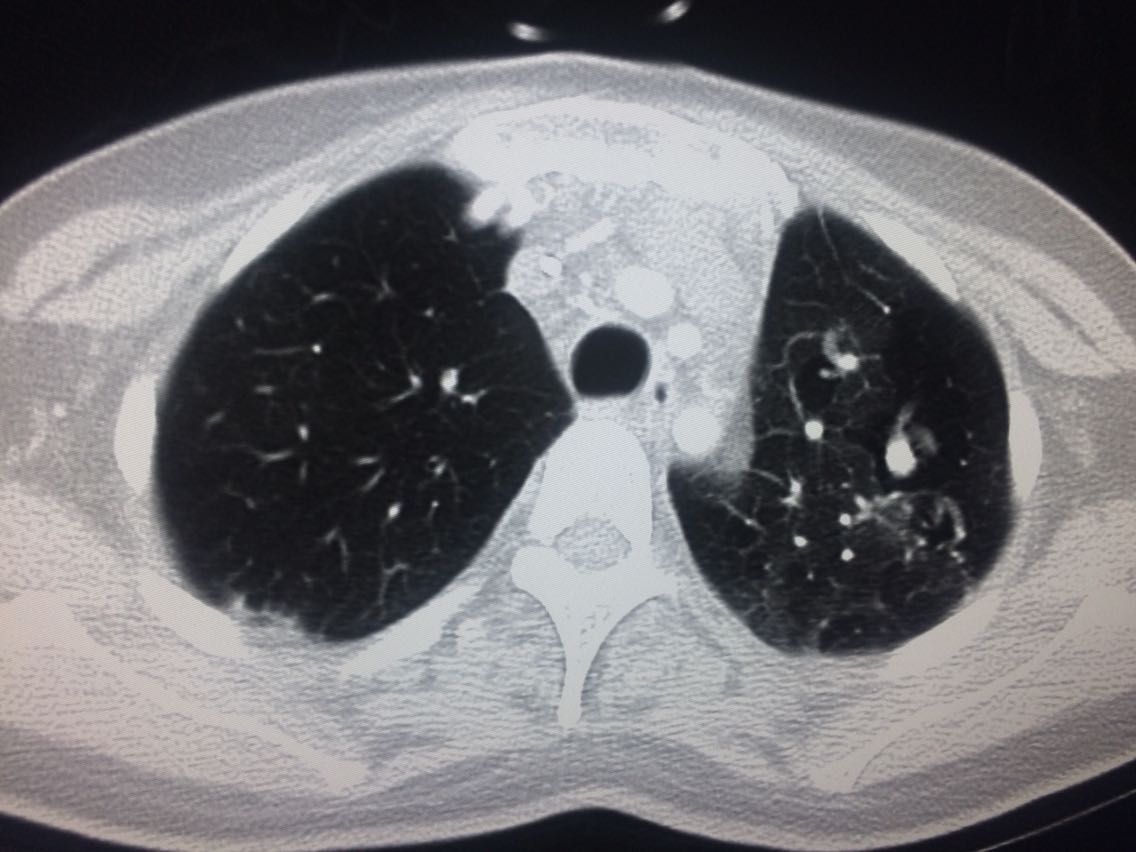

诊断,肺动脉高压。 鉴别诊断,肺动脉栓塞。 影像诊断,肺动脉高压,肺门区出现残根征,肺动脉扩张,肺动脉段膨隆,心影增大。CTA见迂曲增宽的肺动脉。 肺栓塞,影像可见典型充型缺损影,伴随肺纹理的减少。 治疗以对症处理为主,病人病史14年。 讨论诊断和鉴别诊断? 随访,症状好转。